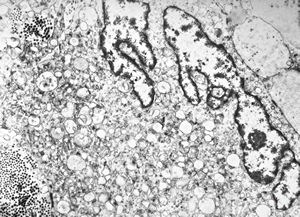

F,68y. | xanthomatous cell in atherosclerotic plaque - a. vertebralis